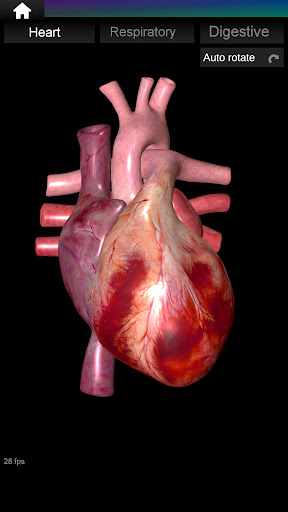

Internal Organs in 3D Anatomy لـ Vodafone Smart N9 Lite

(الأجهزة الداخلية في)

Internal Organs 3D Anatomy 3.4

يمكنك هنا تنزيل ملف حزمة تطبيق أندرويد "Internal Organs 3D Anatomy" الخاصة بجهازVodafone Smart N9 Lite مجانًا، نسخة ملف حزمة تطبيق أندرويد - 3.4 للتحميل على Vodafone Smart N9 Lite اضغط ببساطة على هذا الزر. إنه سهل وآمن. نحن نقدم فقط ملفات حزمة تطبيق أندرويد الأصلية. إذا انتهكت أية مواد موجودة في الموقع حقوقك قم بإبلاغنا من خلال